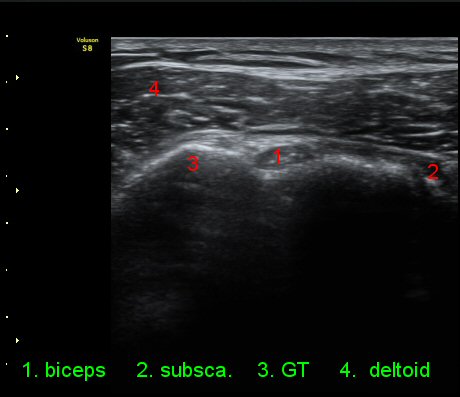

2049205267_d4912430_US181205109.jpg

2049205267_a5fe3a8a_US181253111.jpg

2049205267_e81a53aa_US181338113.jpg